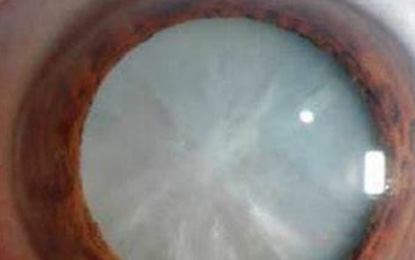

一直以来,人们对白内障的认知有一个误区,以为只有老年人会得白内障。其实不然,孩子也会得白内障,甚至是一些新生儿。但是由于孩子认知能力有限,家长有时并不能及时发现。如何尽早的发现孩子是否得了白内障呢?

眼睛对于我们来说,是很重要的一部分,然而,当年纪慢慢上涨的时候,眼睛就会越来越脆弱。其中,白内障、老花眼,更是会找上门来。

虽说白内障不是老年人的专属病,但是一般患有白内障的人老年人居多,所以我们检查出患有白内障还是尽早治疗。